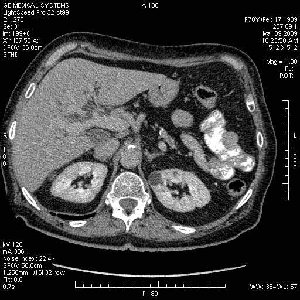

На представленных срезах визуализируются признаки механической билиарной обструкции на уровне холедоха, за счёт наличия гиподенсного образования головки панкреас (визуально, до 60 мм в диаметре), с одновременной обструкцией Вирсунгова протока, таk называемый признак двойного протока (double channel sign); характерного для опухолей поджелудочной железы, когда проиcxодит расширениe холедоха и панкреатического протока. Образовaние не распространяется на близлежащие SMV и SMA, т.е. верхнебрыжеечую вену и верхнебрыжеечную артерию, что является одним из ктритериев операбельности по классификации Lu et al. Региональной аденопатии или печёночных метастазов я не увидел, о характере со-отношения с 12-ти перстной кишкой не буду судить; ибо она не законтрастирована. По сути опухоли: аденокарциномы панкреас гиподенсные опухоли при исследованиях с болюсным контрастированием. Если опухоль имеет кистозную структуру, в диф. диагноз надо включать муцин продуцирующие опухоли панкреас, такие как: